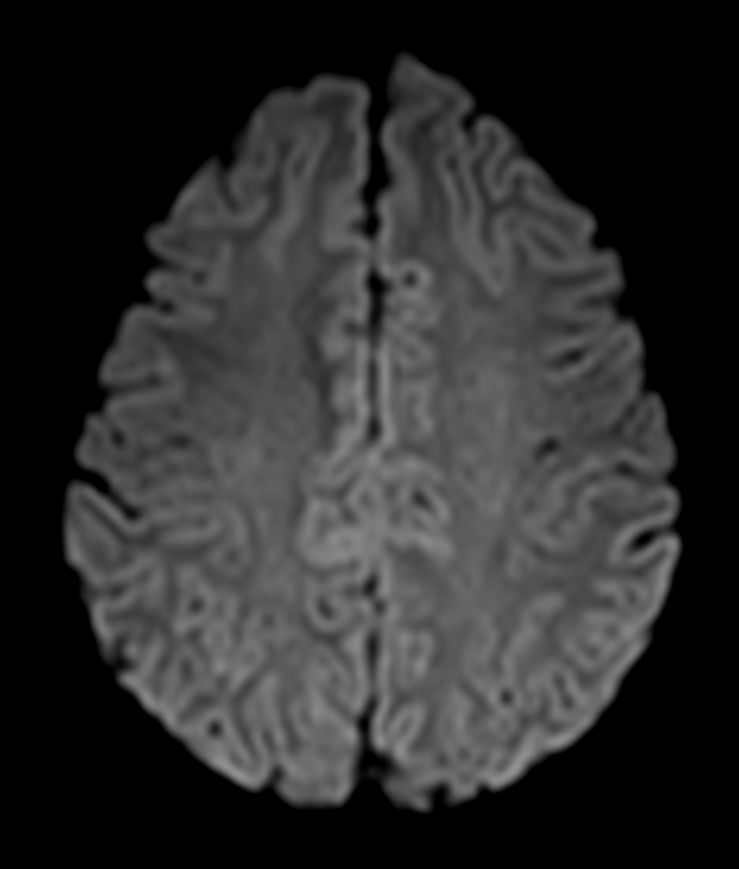

SWI sequence has a high sensitivity to enhance contrast for deoxygenated (venous) blood or calcium deposits. This may help, when used in combination with other clinical information, in the diagnosis of various neurological pathologies. 3D imaging lets you acquire high resolution data in multiple directions in one scan. Isotropic voxel size enables reformats in any plane without loss of resolution. FLAIR* requires offline post processing combining the contrast of 3D FLAIR and 3D SWI EPI into a single image. This enables the visualization of Central Vein Sign, mapping subcortical veins onto 3D FLAIR contrast images.